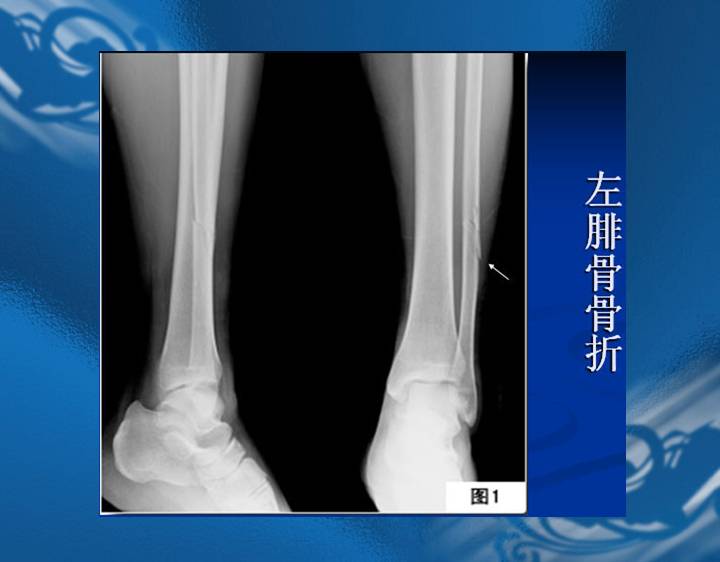

执业医师资格考试“实践技能”影像学辅导资料